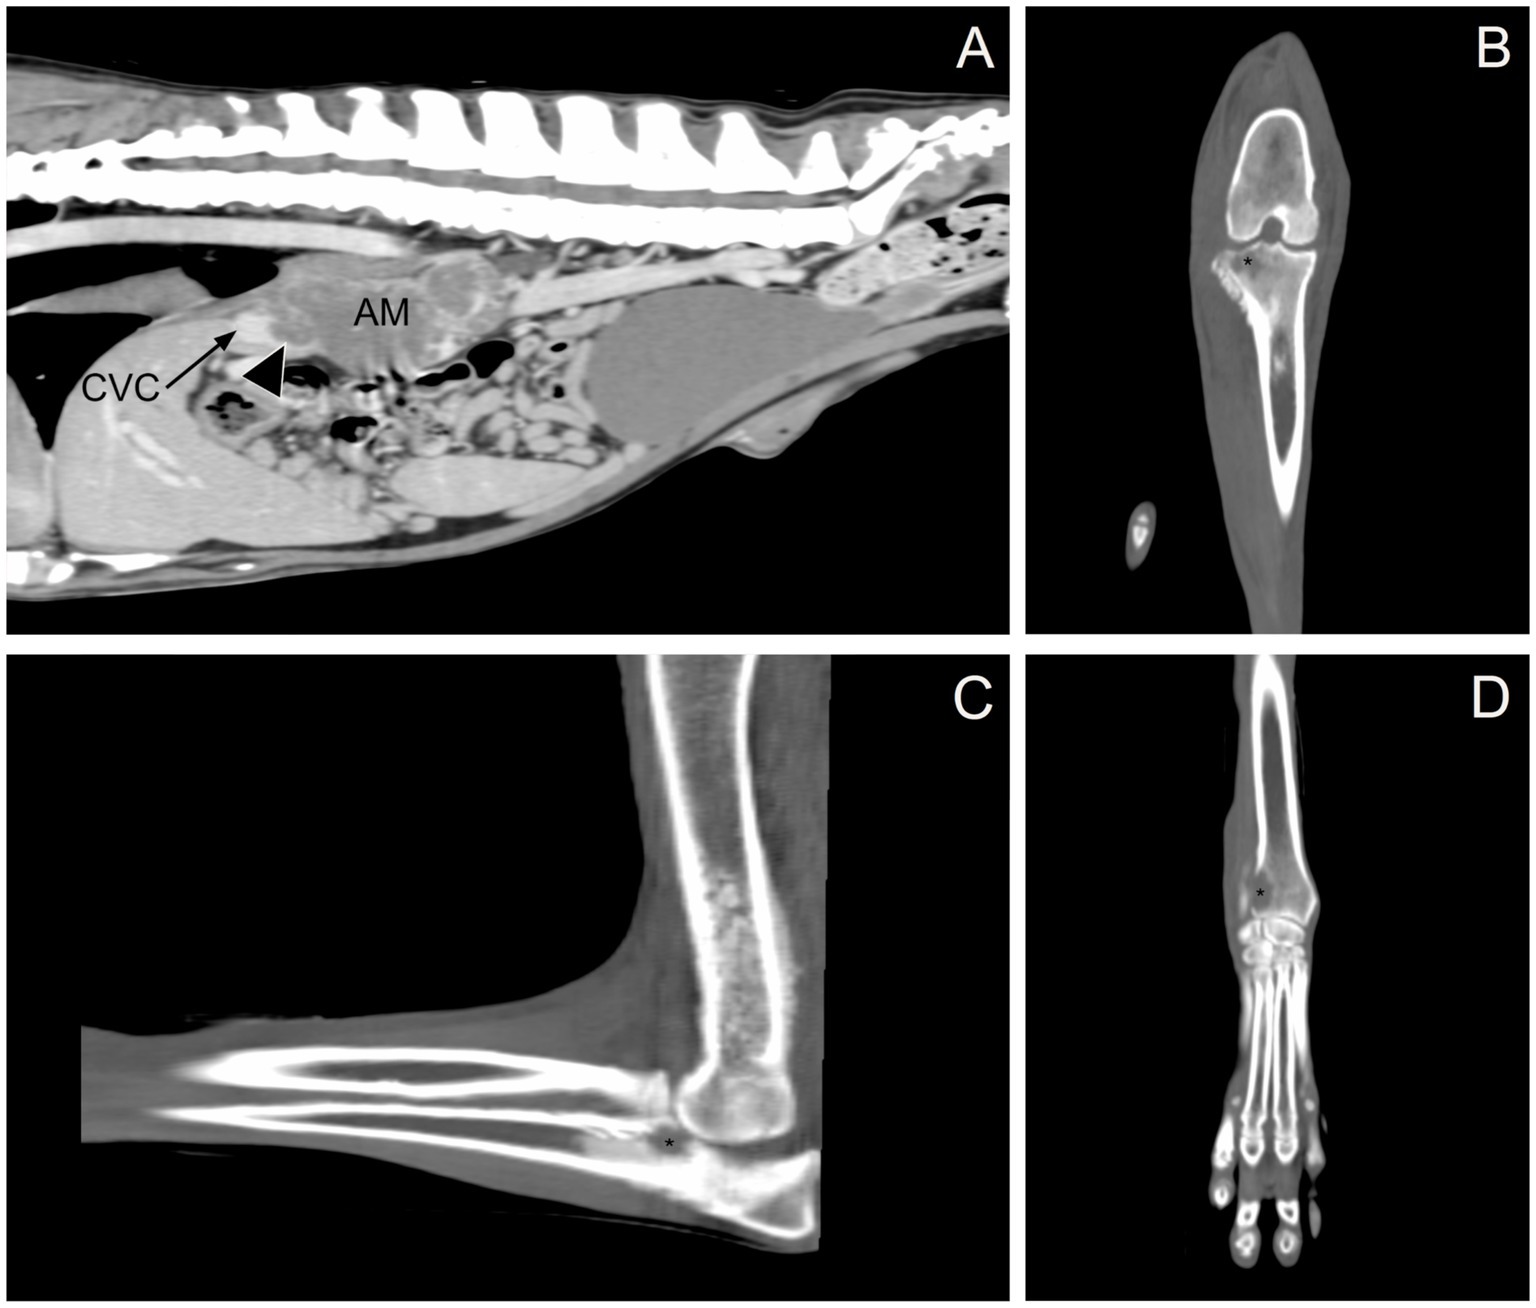

Given the previous finding of an adrenal mass in conjunction with joint swelling not attributable to inflammatory or infectious arthropathies, a CT scan of the thorax, abdomen, and thoracic and pelvic limbs was performed to investigate the local extent of the mass and for any metastatic disease. Imaging revealed the following abnormalities: (1) a large mass in the right adrenal gland extending into the caudal vena cava (Figure 1A); (2) nodular left adrenomegaly; (3) ill-defined, variably sized nodules and masses in multiple liver lobes; (4) ill-defined, variably sized nodules and masses in all lung lobes; (5) multifocal intra-abdominal lymphadenomegaly (medial iliac, internal iliac, splenic, hepatic, and lumbar aortic); and (6) multifocal regions of osteolysis involving the cervical, thoracic, lumbar, sacral, and caudal vertebrae, ribs, pelvis, right and left scapulae, right and left humeri, distal right and left radius, proximal right ulna, right radial carpal bone, distal right and left femur, and proximal right tibia (Figures 1BD). Focal soft tissue thickening adjacent to the right carpus, elbow, and stifle was associated with osteolytic lesions in the distal right radius, right radial carpal bone, proximal right ulna, and proximal right tibia, resulting in periarticular swelling instead of true joint swelling (i.e., a true increase in synovial volume). Imaging findings supported primary malignant neoplasia of the right adrenal gland with local vascular invasion and widespread distant metastasis. Because of the extent of the disease in this dog and the associated poor prognosis, humane euthanasia was recommended.

Figure 1. Computed tomography. (A) Sagittal, post-contrast image showing the right adrenal gland mass (AM) invading the caudal vena cava (CVC, black arrow; invasion, arrowhead). (B) Dorsal, pre-contrast image showing osteolysis in the proximal right tibia (black asterisk). (C) Sagittal, pre-contrast image showing osteolysis in the proximal right ulna (black asterisk). (D) Dorsal, pre-contrast image showing osteolysis in the distal right radius (black asterisk).